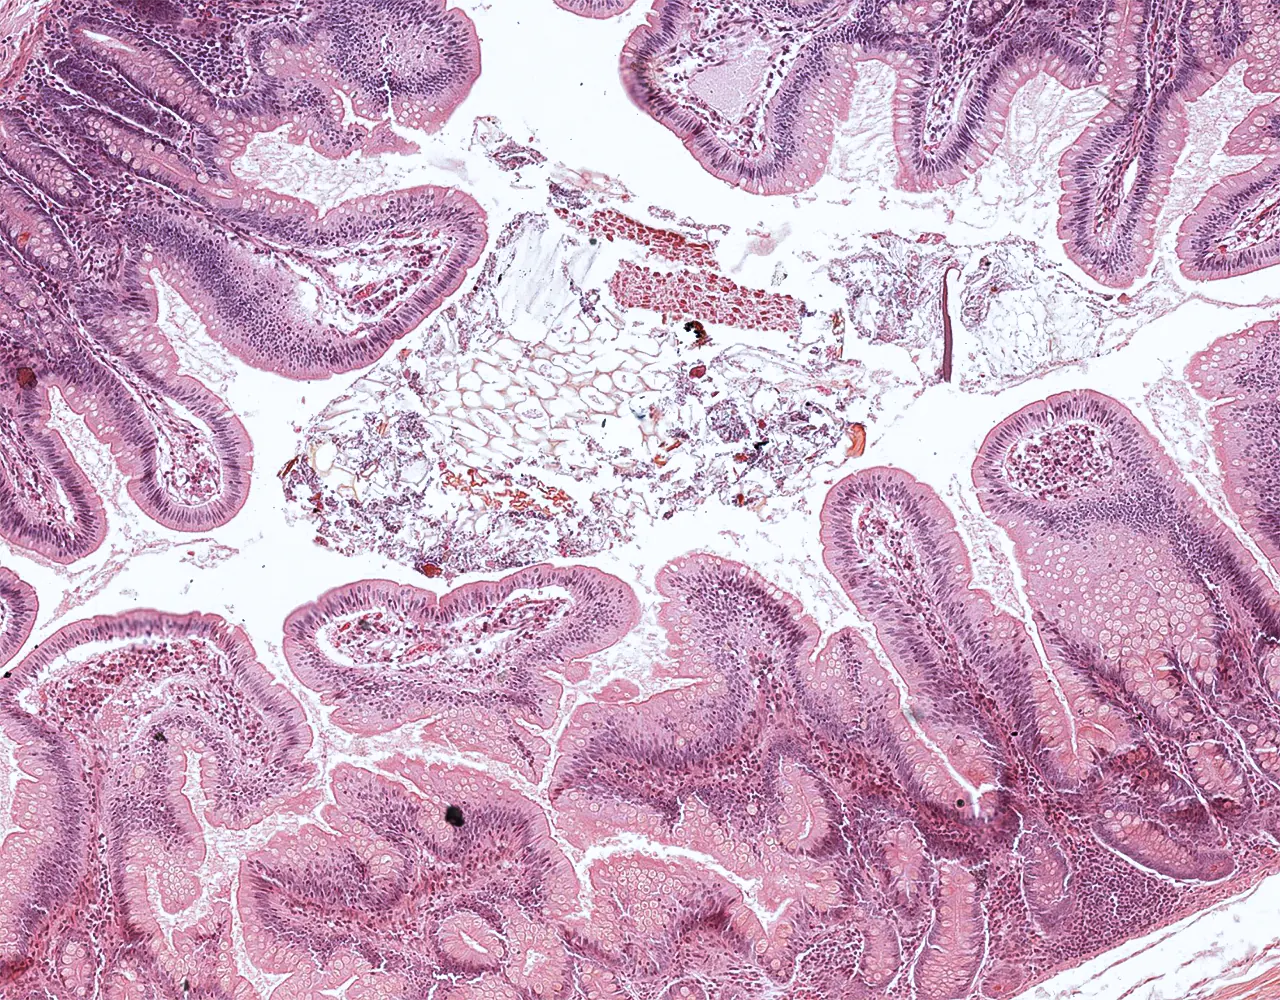

- The absorptive surface area of the small intestine is amplified by three structural levels: plicae circulares, villi, and apical microvilli forming the brush border.

- Microscopically, the wall is composed of 4 layers from the inside outward: mucosa, submucosa, muscularis propria, and serosa.